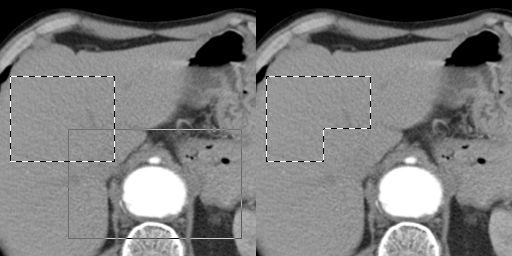

In the examples is used the selection rectangle tool.

Selection Addition

Before you select the second area hold down the <Shift> key of the keyboard, and then use your mouse for the second selection.

Selection Subtraction

Before you select the second area hold down the <Ctrl> key of the keyboard, and then use your mouse for the second selection.

Selection Intersection (common area)

Before you select the second area hold down the <Shift> and <Ctrl> keys of the keyboard, and then use your mouse for the second selection.